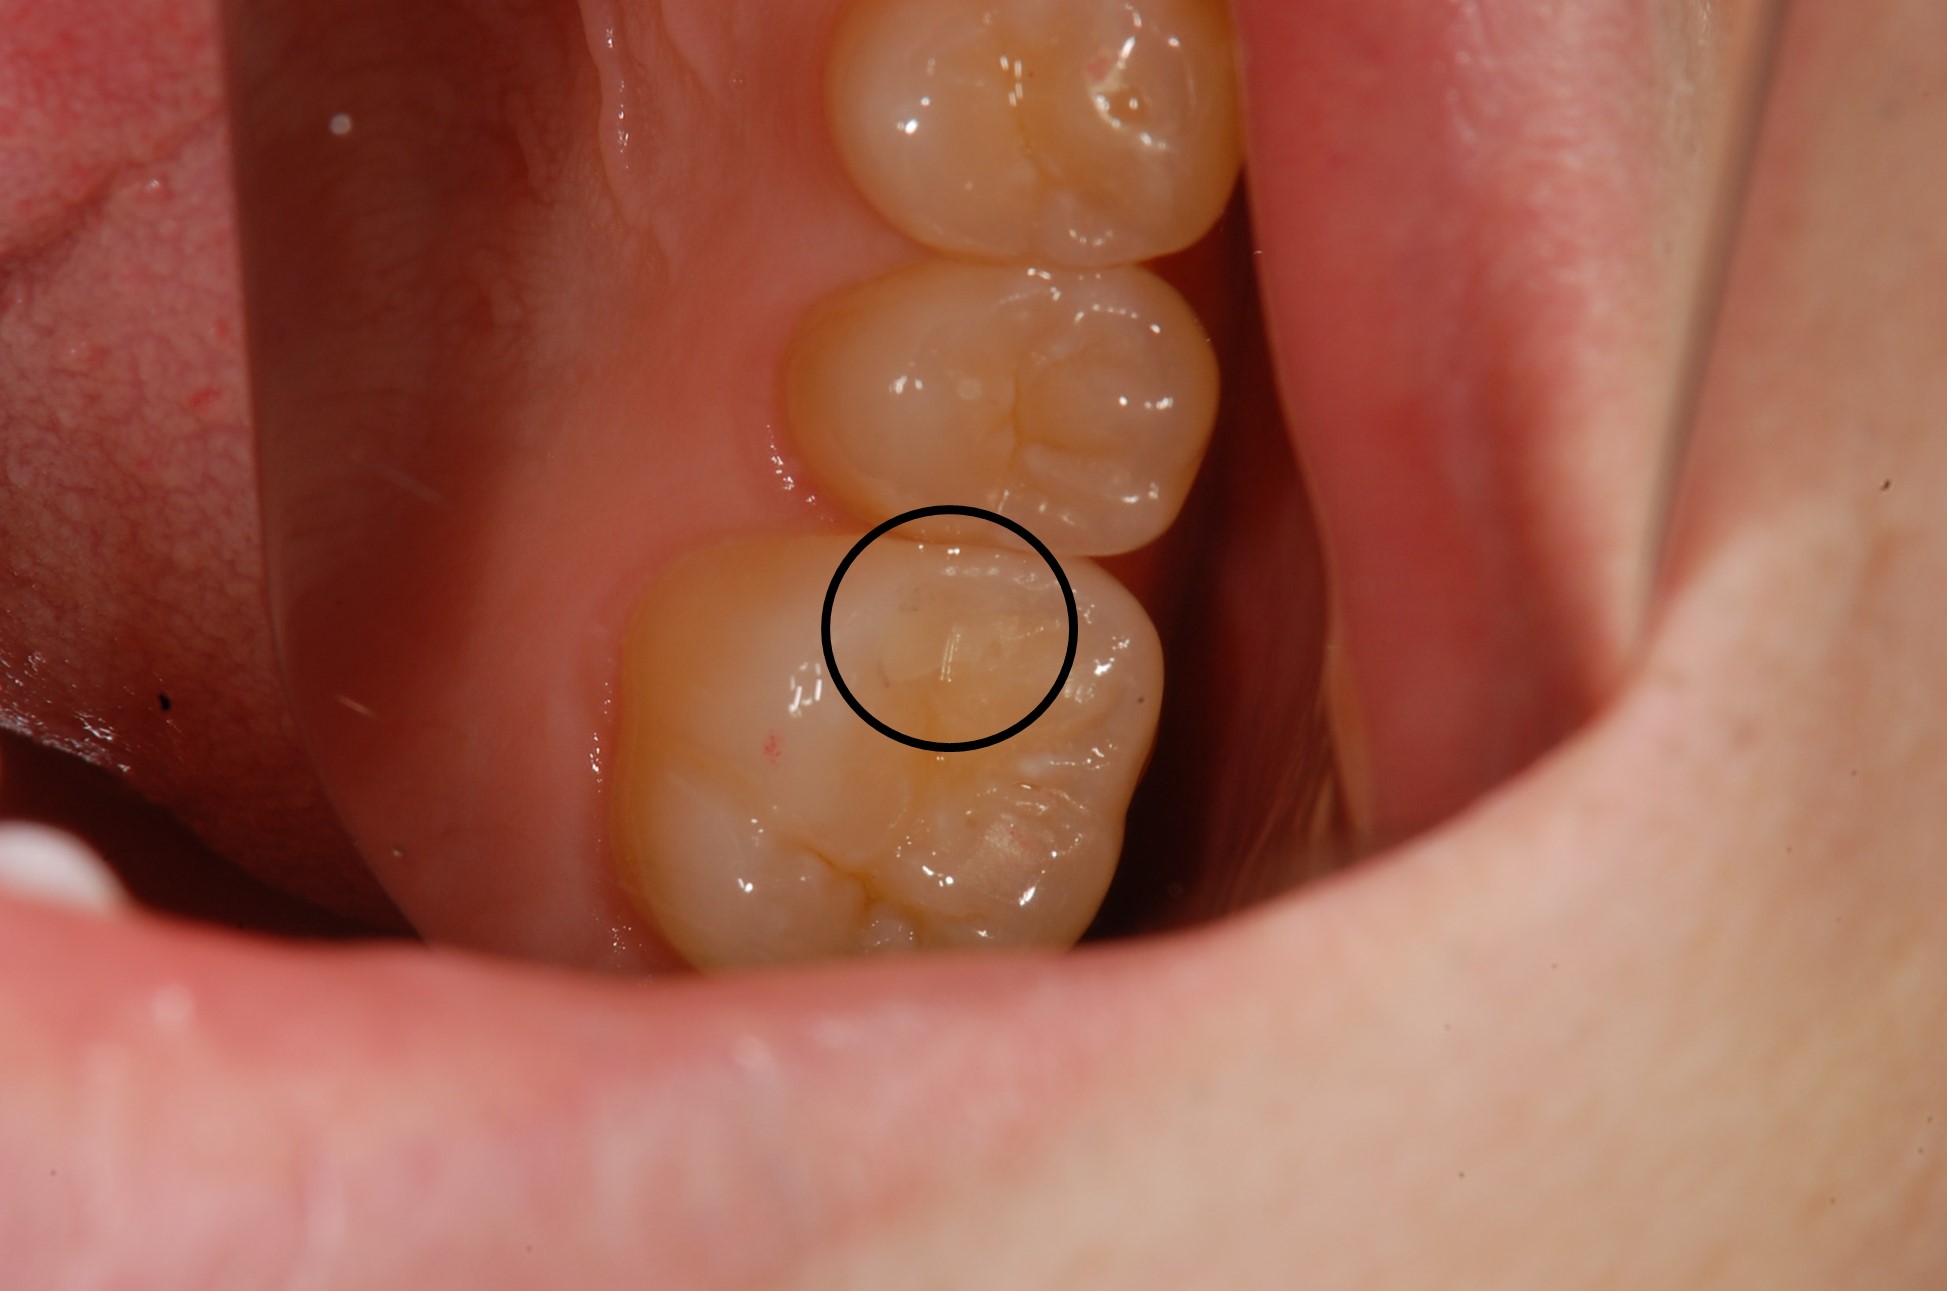

〇で示した部分が該当部分の虫歯を除去した状態です。

ここにコンポジットレジンを充填します。